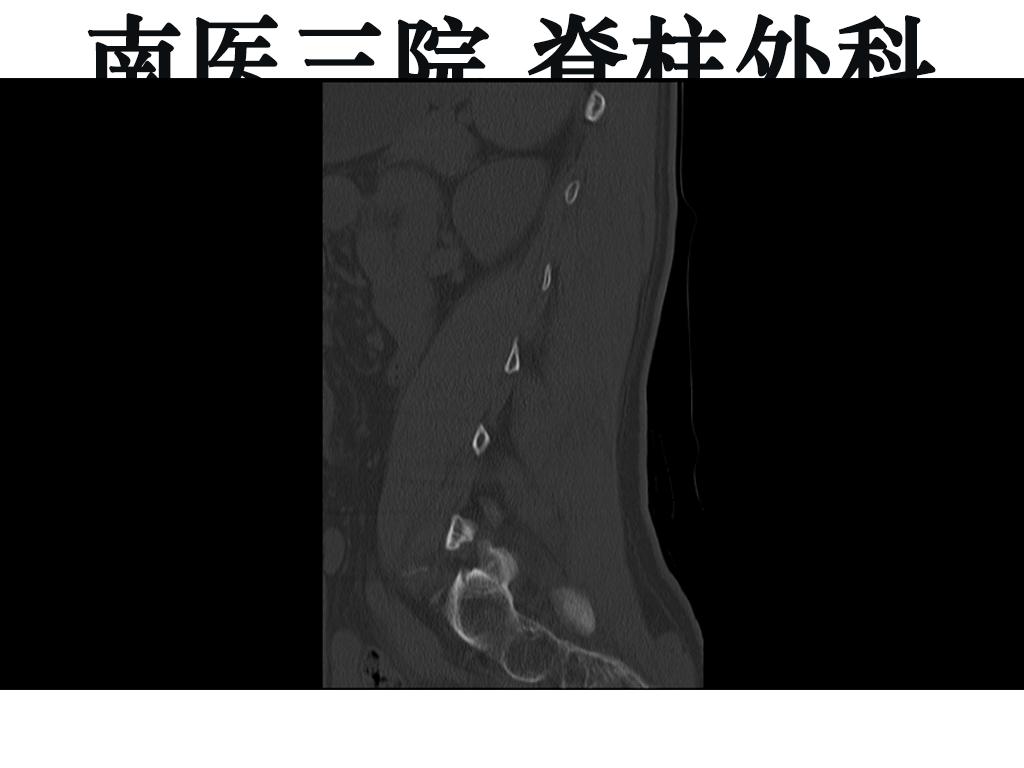

腰椎峡部裂术后